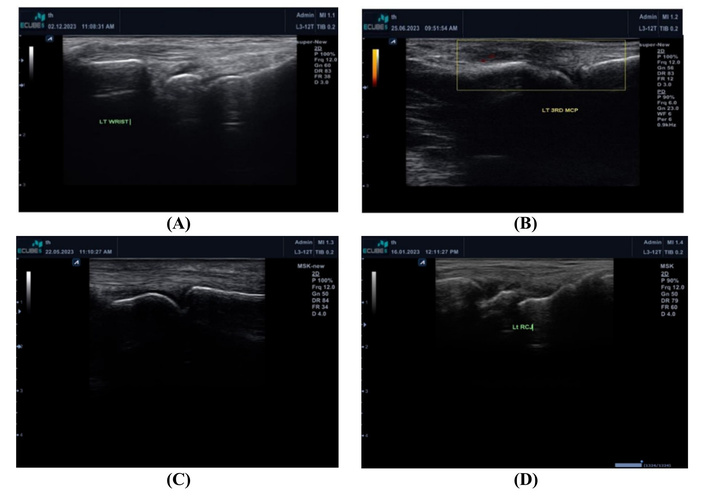

Figure 2 shows examples of our MSUS findings in the RA groups and the control group.

Examples of the MSUS findings in the RA groups and the control group. (A) Normal LT wrist in the control group; (B) Grade 2 synovitis in left 3rd MCP in a patient with power Doppler in RA active patient; (C) Grade 1 synovitis in LT 2nd PIP in a patient with inactive RA; (D) Grade 1 synovitis in LT wrist in the control group. Grade 1 synovitis was accepted especially in the dominant hand in the control group. LT: left; MCP: metacarpophalangeal joint; MSUS: musculoskeletal ultrasonography; PIP: proximal interphalangeal joint; RA: rheumatoid arthritis.